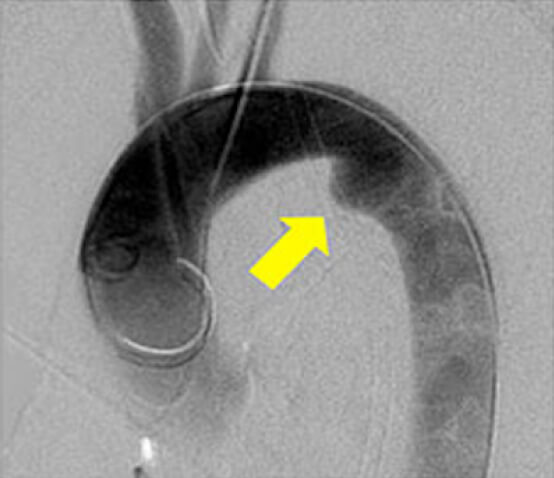

内腸骨動脈瘤の解剖学的な成因についての研究

内腸骨動脈瘤は、他の動脈瘤と同様に放置すると破裂し生命の危険がある病気です。しかしその発生原因は解明されていません。私達はこれまでの手術症例の解析から、内腸骨動脈の枝である上臀動脈と下臀動脈が、長い共通幹を有する特徴的な内腸骨動脈の分岐パターン(下図におけるGroup B)が、内腸骨動脈瘤の存在と関連することを発見しました。先天的な血管の枝分かれのパターンが、血行動態を通じて動脈壁に影響を及ぼし、瘤の形成に関与している可能性があります。

内腸骨動脈分岐パターンの例

(右:Group B、左:Group A)